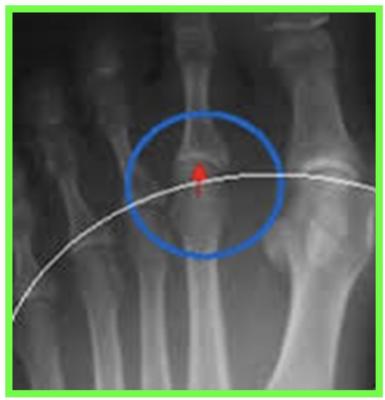

HALLUX RIGIDUS

L’hallux rigidus (ou hallux limitus) est le nom donné à l’arthrose de l'articulation métatarso phalangienne de l’hallux. Il s’agit d’une maladie dégénérative de l’articulation métatarso-phalangienne (MTP) et de la sesamoido métatarsienne, le plus souvent sans cause connue (idiopathique).

DIAGNOSTIC

Deux stades :

Hallux rigidus au stade de douleurs

STADE 1 : HALLUX DOLOROSUS

DOULEUR +++Diminution de la flexionPincement de l’interligne

Hallux rigidus au stade de raideurs

STADE 2 : HALLUX LIMITUS

Douleur atténuéeLIMITATION DE LA FLEXIONVolumineuse exostose dorsalePincement majeur, ostéophytesOn constate cliniquement un aspect globuleux de la MTP de l’hallux, avec une excroissance osseuse (ostéophyte dorsal) gênant le chaussage. Limitation douloureuse de la flexion dorsale de la MTPParfois sensation de craquement à la mobilisation de la MTPL'hallux est le plus souvent normo-axé

Radiographie des pieds face et profil en charge +++ avant consultation d’un spécialiste

Étude de l’architecture global du pied, de l’état articulaire à la recherche d’une arthrose, fracture de contrainte, et mesure des angles

Le pincement de l’interligne articulaire et les ostéophytes ci-dessus sont caractéristiques de l’hallux rigidus